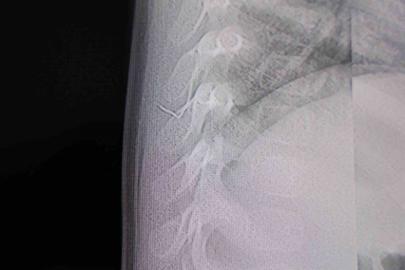

Edinilen bilgilere göre, Adıyaman merkez Siteler Mahallesi Örenli TOKİ yakınlarında M.Y., isimli kişi kimliği belirsiz bir şahsın silahlı saldırısına uğradı. Silahtan çıkan merminin vücuduna isabet etmesi sonucu yaralanan M.Y., olay yerine gelen sağlık ekiplerince yapılan ilk müdahalenin ardından Adıyaman Eğitim ve Araştırma Hastanesi’ne kaldırıldı. Polis ekipleri, olayı gerçekleştiren ve daha sonra olay yerinden kaçan şahsın yakalanması için çalışma başlattı.